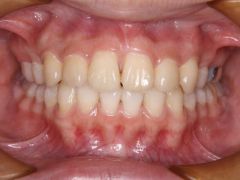

初診時年齢15歳の女子 上顎前歯の叢生を主訴として来院された。

セファログラム写真の分析から下顎が後退した過蓋咬合を伴う骨格性上顎前突であると診断し、上顎舌側、下顎唇側マルチブラケット装置を使用して、口蓋正中部に矯正用アンカースクリューを併用して動的治療を行った。動的治療期間1年7カ月間